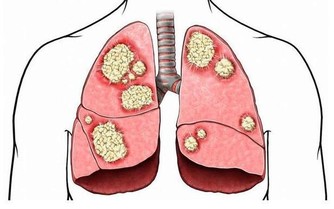

3. 患有哮喘

服用阿司匹林會導致支氣管出現痙攣,使呼吸出現障礙。這種情況對於哮喘患者來說,可能是致命的危險。因此,如果你患有哮喘,一定要遠離阿司匹林,避免發生意外狀況。